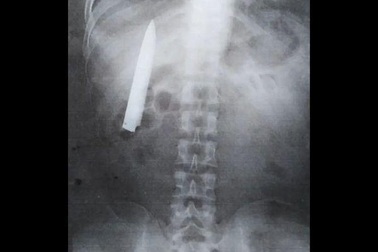

Dao găm trong ngực hơn 1 năm mà không biếtBị đâm trên đường đi làm về từ 14 tháng trước, 14 tháng sau người đàn ông sốc nặng khi biết trong ngực mình có... dao găm.